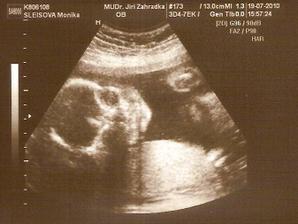

11.5. NT screening, jsem 13+5 a teď čekáme.....12.5. výsledky jsou v normě! 🙂